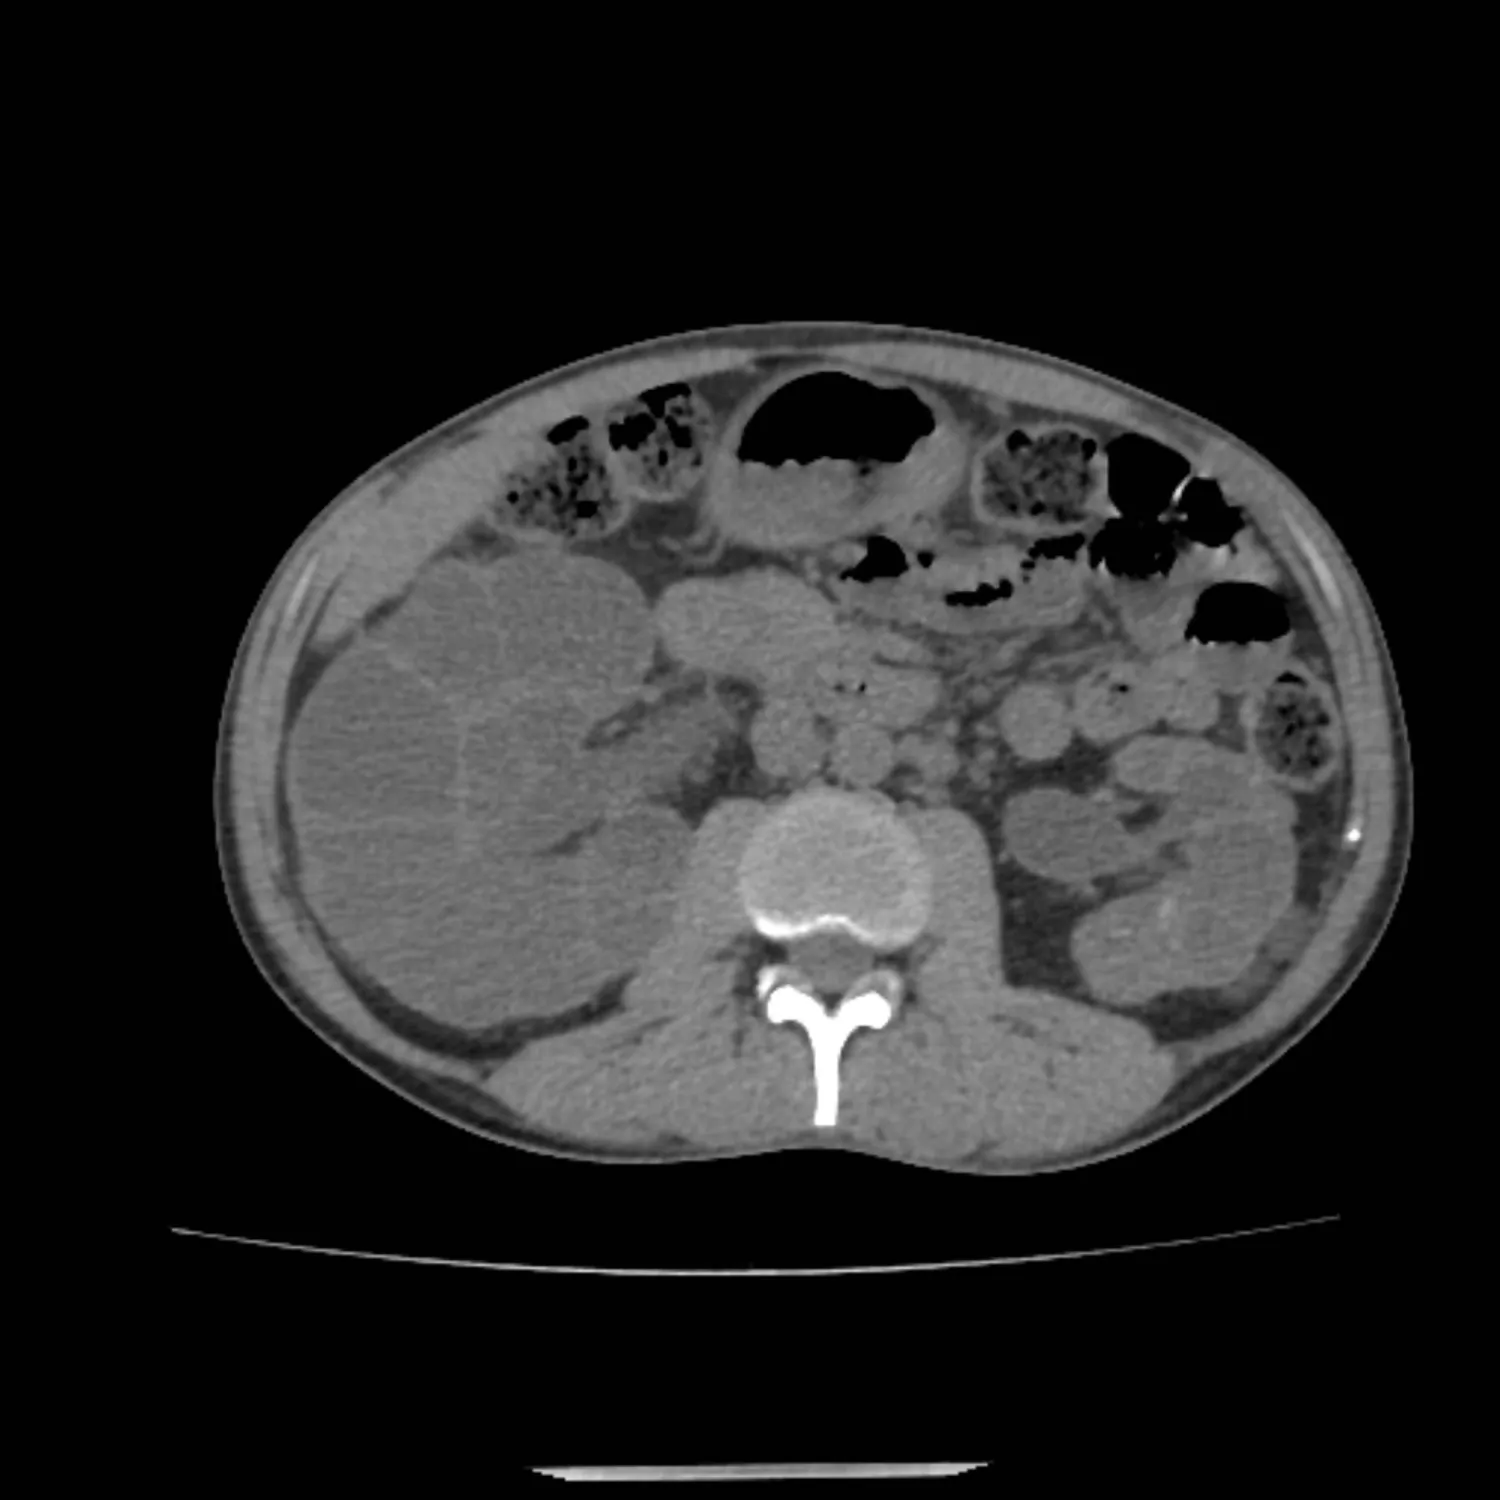

ينتج المرض عن طفرات في جيني PKD1، وPKD2، ما يؤدي إلى تكوّن أكياس مملوءة بالسوائل في الكلى. ومع مرور الوقت تسبب هذه الأكياس ارتفاع ضغط الدم، والتهابات، وألماً شديداً، وتنتهي غالباً بفشل كلوي يستدعي الغسيل، أو الزراعة.

كما حدد الباحثون 39 طفرة في جين PKD1 لدى مرضى مرض الكلى متعدد الكيسات السائد Autosomal dominant polycystic kidney disease (ADPKD)، وتمكنوا في المختبر من تصحيح نحو ثلثها. وعند اختبار التقنية على خلايا مأخوذة من بول المرضى استعادت الخلايا إنتاج بروتين (بوليسيستين-1 polycystin-1) الضروري لوظائف الكلى. وفي تجارب على فئران مصابة أظهرت النتائج انخفاضاً ملحوظاً في عدد وحجم الأكياس الكلوية، وهو تقدم مهم، لأن العلاج الحالي لا يعالج هذه المشكلة.